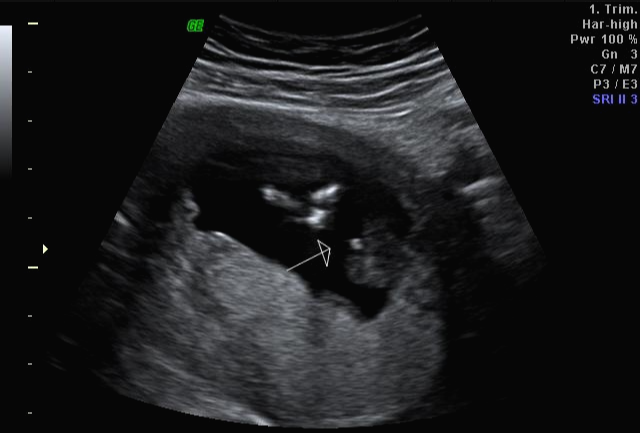

한 달 뒤인 17차 때 다시 사설로 가서 초음파 검사를 받았는데 검사해주시는 분 께서 한참을 보시더라고요~ 그러면서 어떻게 보면 딸 같다고 하셔서... 응? 100프로 아들이라 해서... 다 아들껄로 준비하고 있는데.. 무슨 소리지? 하고 다시 한번 봐달라고 하니 아들이라 하시면서 위에 초음파를 보여주셨어요!

한데 기분이 참 찝찝했어요~ 뭔가 숨기고 있는 듯한.. 정확하지 않는 듯한 느낌 ㅋㅋㅋ... 그래서 임신 17주 차부터 아이 용품 구매하는 걸 중단하고 병원에서 20주 차 정밀 초음파 검사를 기다려 보기로... 가족도 다 아들로 알고 있고 벌써 아들 꺼 처럼 보이는 용품들로 준비했기 때문에 성별 반전이 없기를 기대했어요 ㅠㅠ